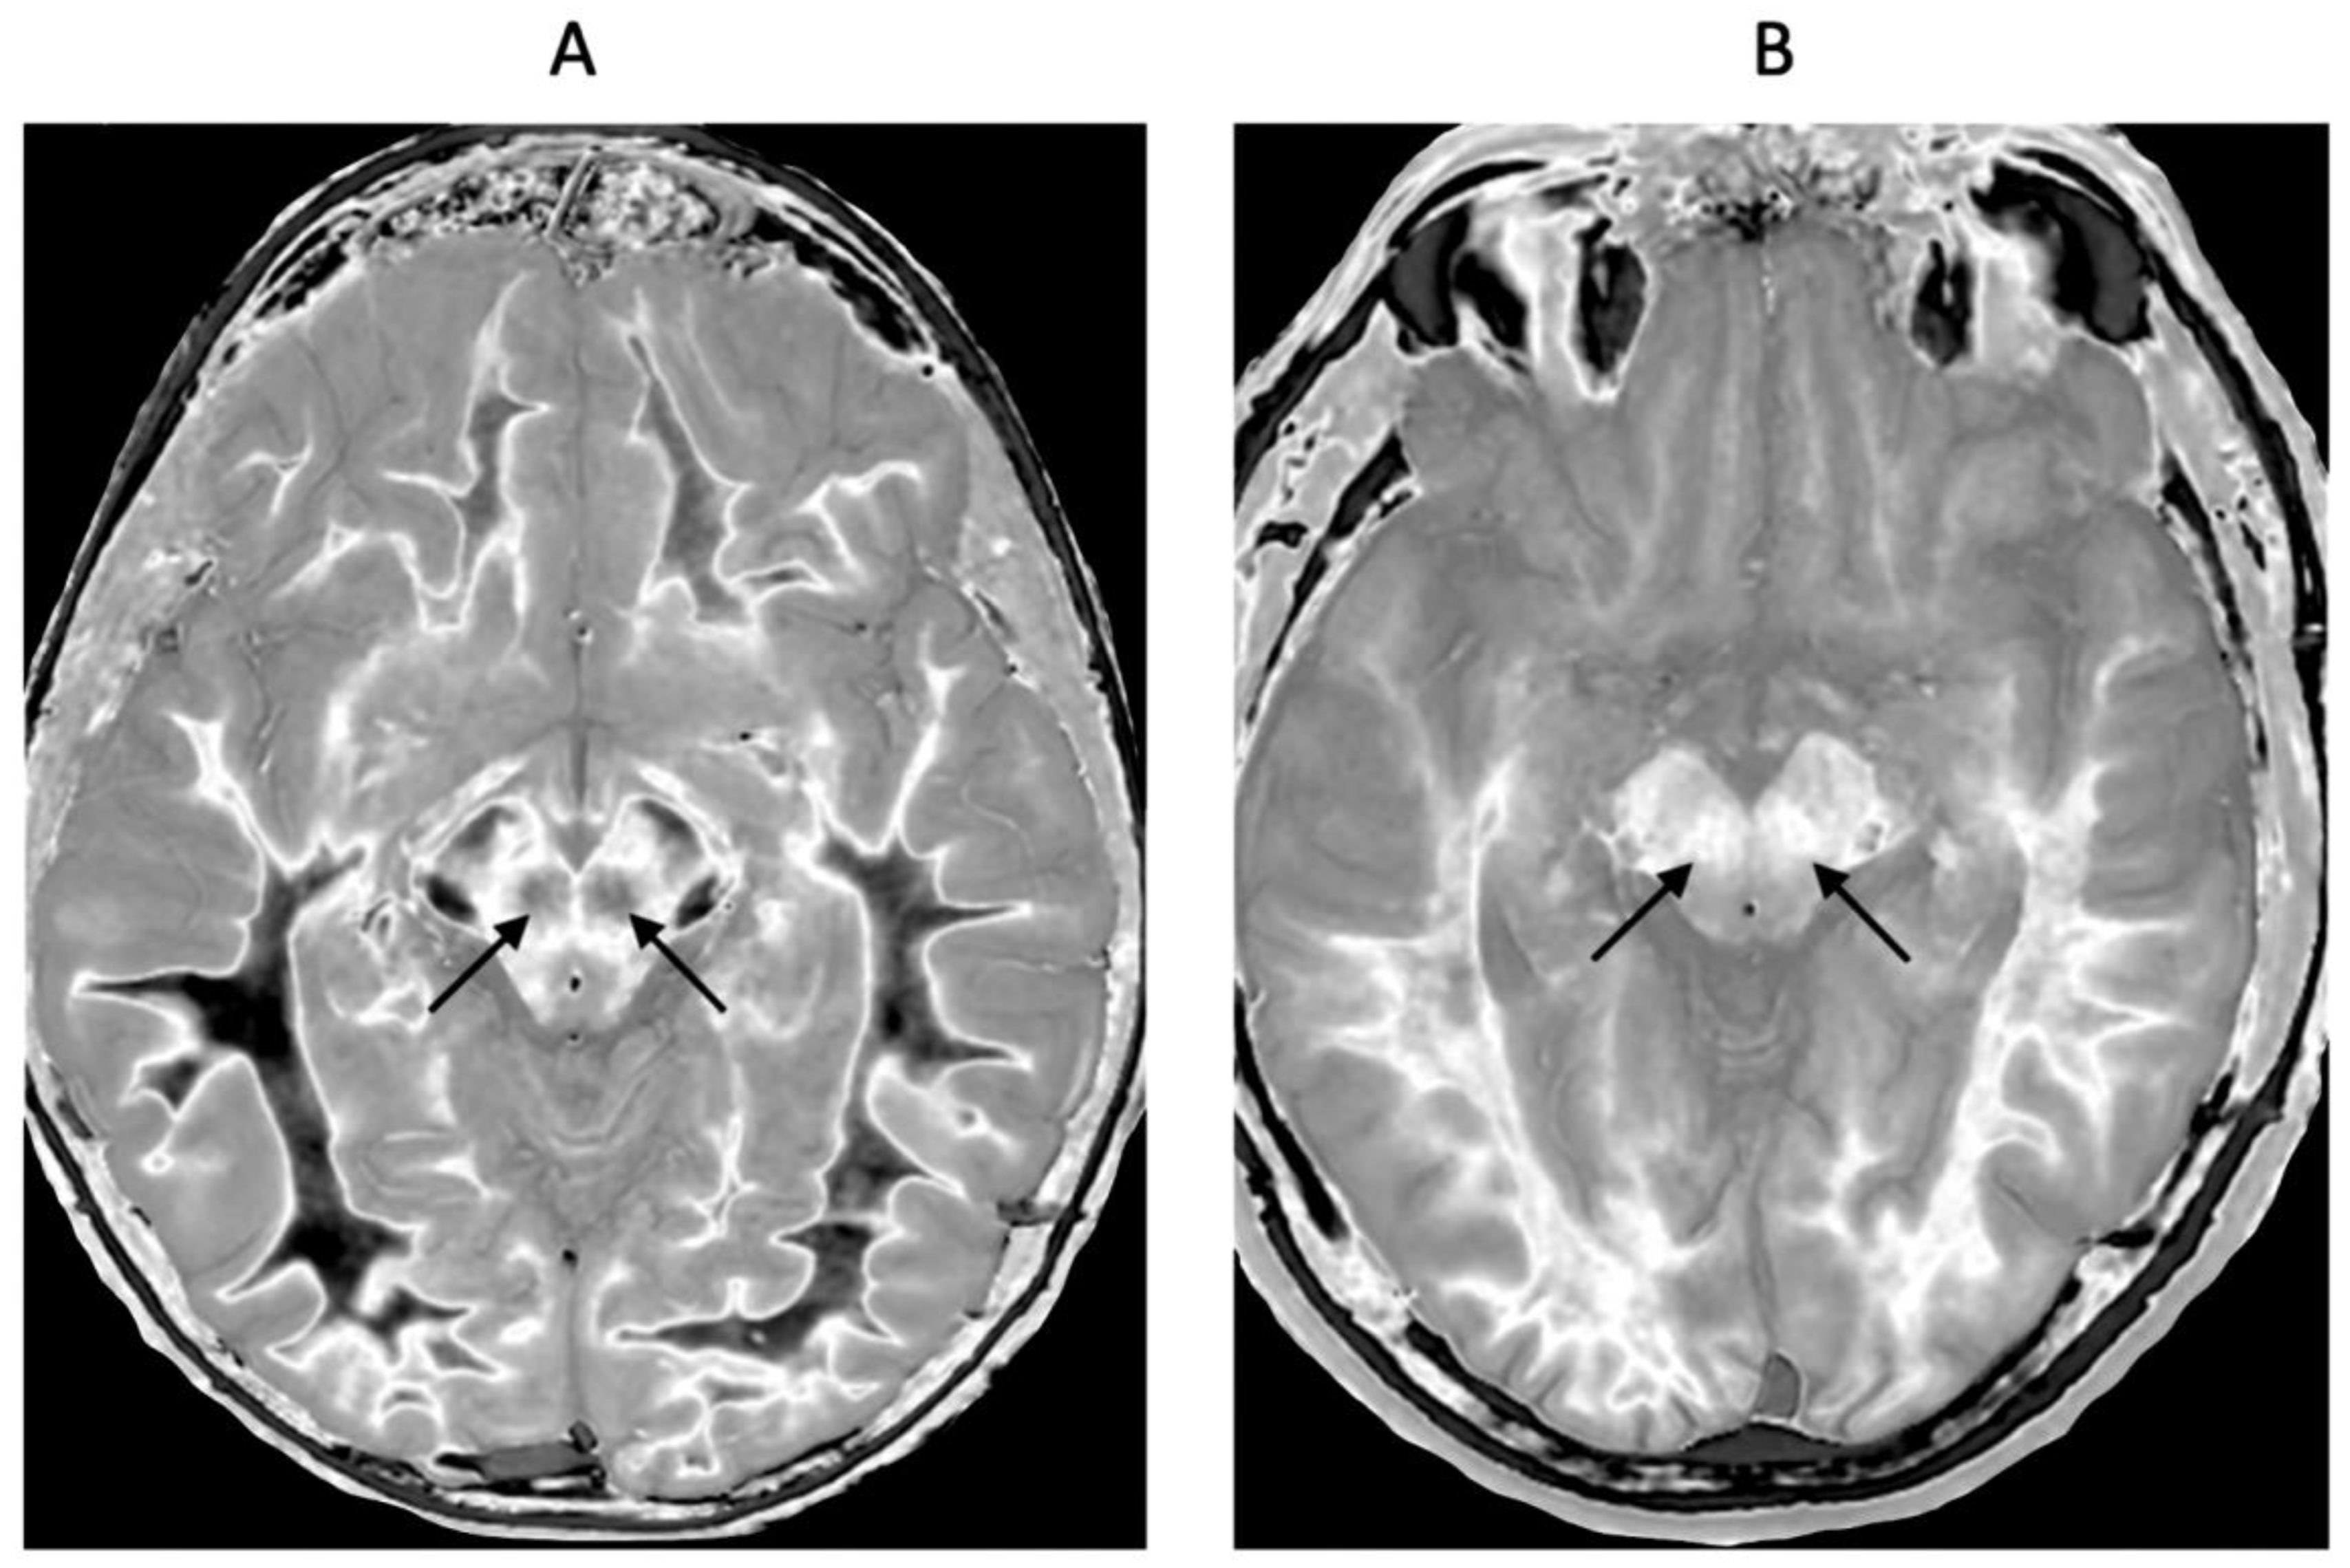

There may also be gray matter changes elsewhere in mTBI. The normal red nuclei have relatively short T

1s resulting in their normal signal being mid-gray in the mD (arrows) (

Figure 14A). They shows a higher signal due to increase in T

1 in a case of mTBI (arrows) (

Figure 14B).

Figure 14.

Red nuclei in an 18-year-old normal control (A) and an 18-year-old male patient with mTBI (B). 2D narrow mD dSIR (T1-BLAIR) images. In (A) the normal control shows low signal in the white matter of the cerebral hemisphere, cortico-spinal tracts and the ascending sensory tracts. The red nuclei (arrows) have an intermediate mid-gray signal. In (B) the patient shows high signal in the cerebral white matter, the corticospinal tracts and the ascending sensory tracts (whiteout sign, grade 4 out of 5). In addition, the red nuclei are higher signal than in (A) (arrows). No abnormality was seen on the T2-FLAIR images in the normal control or patient.